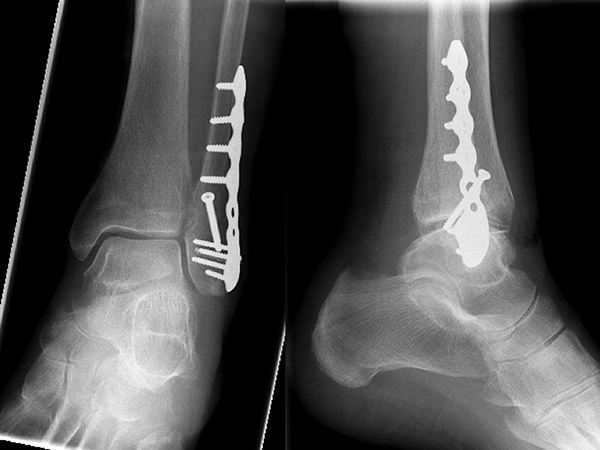

Die Versorgung von AO 44-B Frakturen erfolgt über einen längsverlaufenden lateralen Zugang. In der Regel gelingt eine suffiziente Stabilisierung mittels interfragmentärer Zugschraube (bei langem Frakturverlauf ggf. 2 Zugschrauben) und einer zusätzlichen Neutralisationsplatte (Abbildung 9 & 10).

Bei multifragmentären Frakturen (AO 44-B2.3) oder bei schlechter Knochenqualität sollte die Versorgung mittels winkelstabiler Plattenosteosynthese erwogen werden (Abbildung 11 & 12).